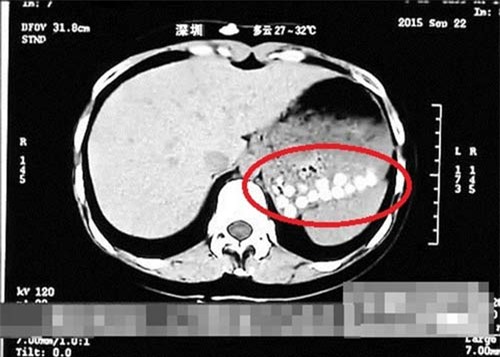

Tháng 10/2015, dư luận Trung Quốc rúng động khi một đoạn phóng sự của Đài Truyền hình Sơn Đông, Trung Quốc tiết lộ sự thật về thành phần làm ra những viên trân châu dẻo dai ngon lành trong những cốc trà sữa được bán ra mỗi ngày chính là từ... đế giày da và lốp xe cũ. Một phóng viên của đài thậm chí còn uống thử trà sữa trân châu sau đó chụp CT sau 40 phút và kết quả ảnh chụp cho thấy dạ dày của phóng viên xuất hiện những chấm nhỏ li ti mãi không tan.